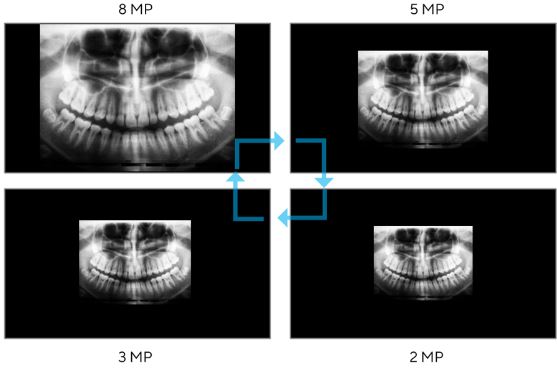

Optimální rozlišení obrazovky

V různých lékařských zobrazovacích modalitách se prezentace lékařských snímků může lišit jak z hlediska velikosti, tak množství zobrazovaných informací. Displeje ASUS HealthCare dokážou simulovat různá rozlišení pro zobrazení různých zdrojů lékařského obrazu s tečkami na obrazovce.